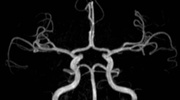

MR-Angiografie (MRA)

• MR-Angiografie ohne Kontrastmittel

• Time of Flight (TOF)-Angiographie

Je nach Fragestellung und Körperregion Gefäßdarstellung ohne Kontrastmittel bei Kontrastmittelunverträglichkeit oder terminaler Niereninsuffizienz möglich.

• MR-Angiographie mit Kontrastmittel

• Erfassung arterieller und venöser Gefäße/Bypässe aller Körperregionen mit 3D-Rekonstruktion